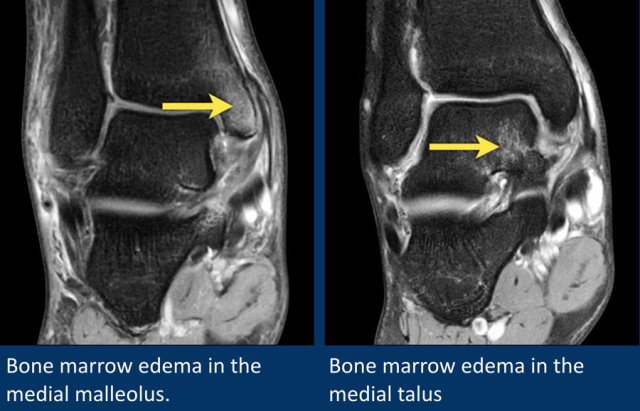

Here two patients with bone marrow edema.

The patient on the left has bone marrow edema in the medial malleolus.

The patient on the right has edema in the medial talus.

Both patients have had an eversion injury, with stretching of the deltoid ligament.

The bone marrow edema in these patients is due to avulsion injury on the insertion sites of the deltoid ligament.